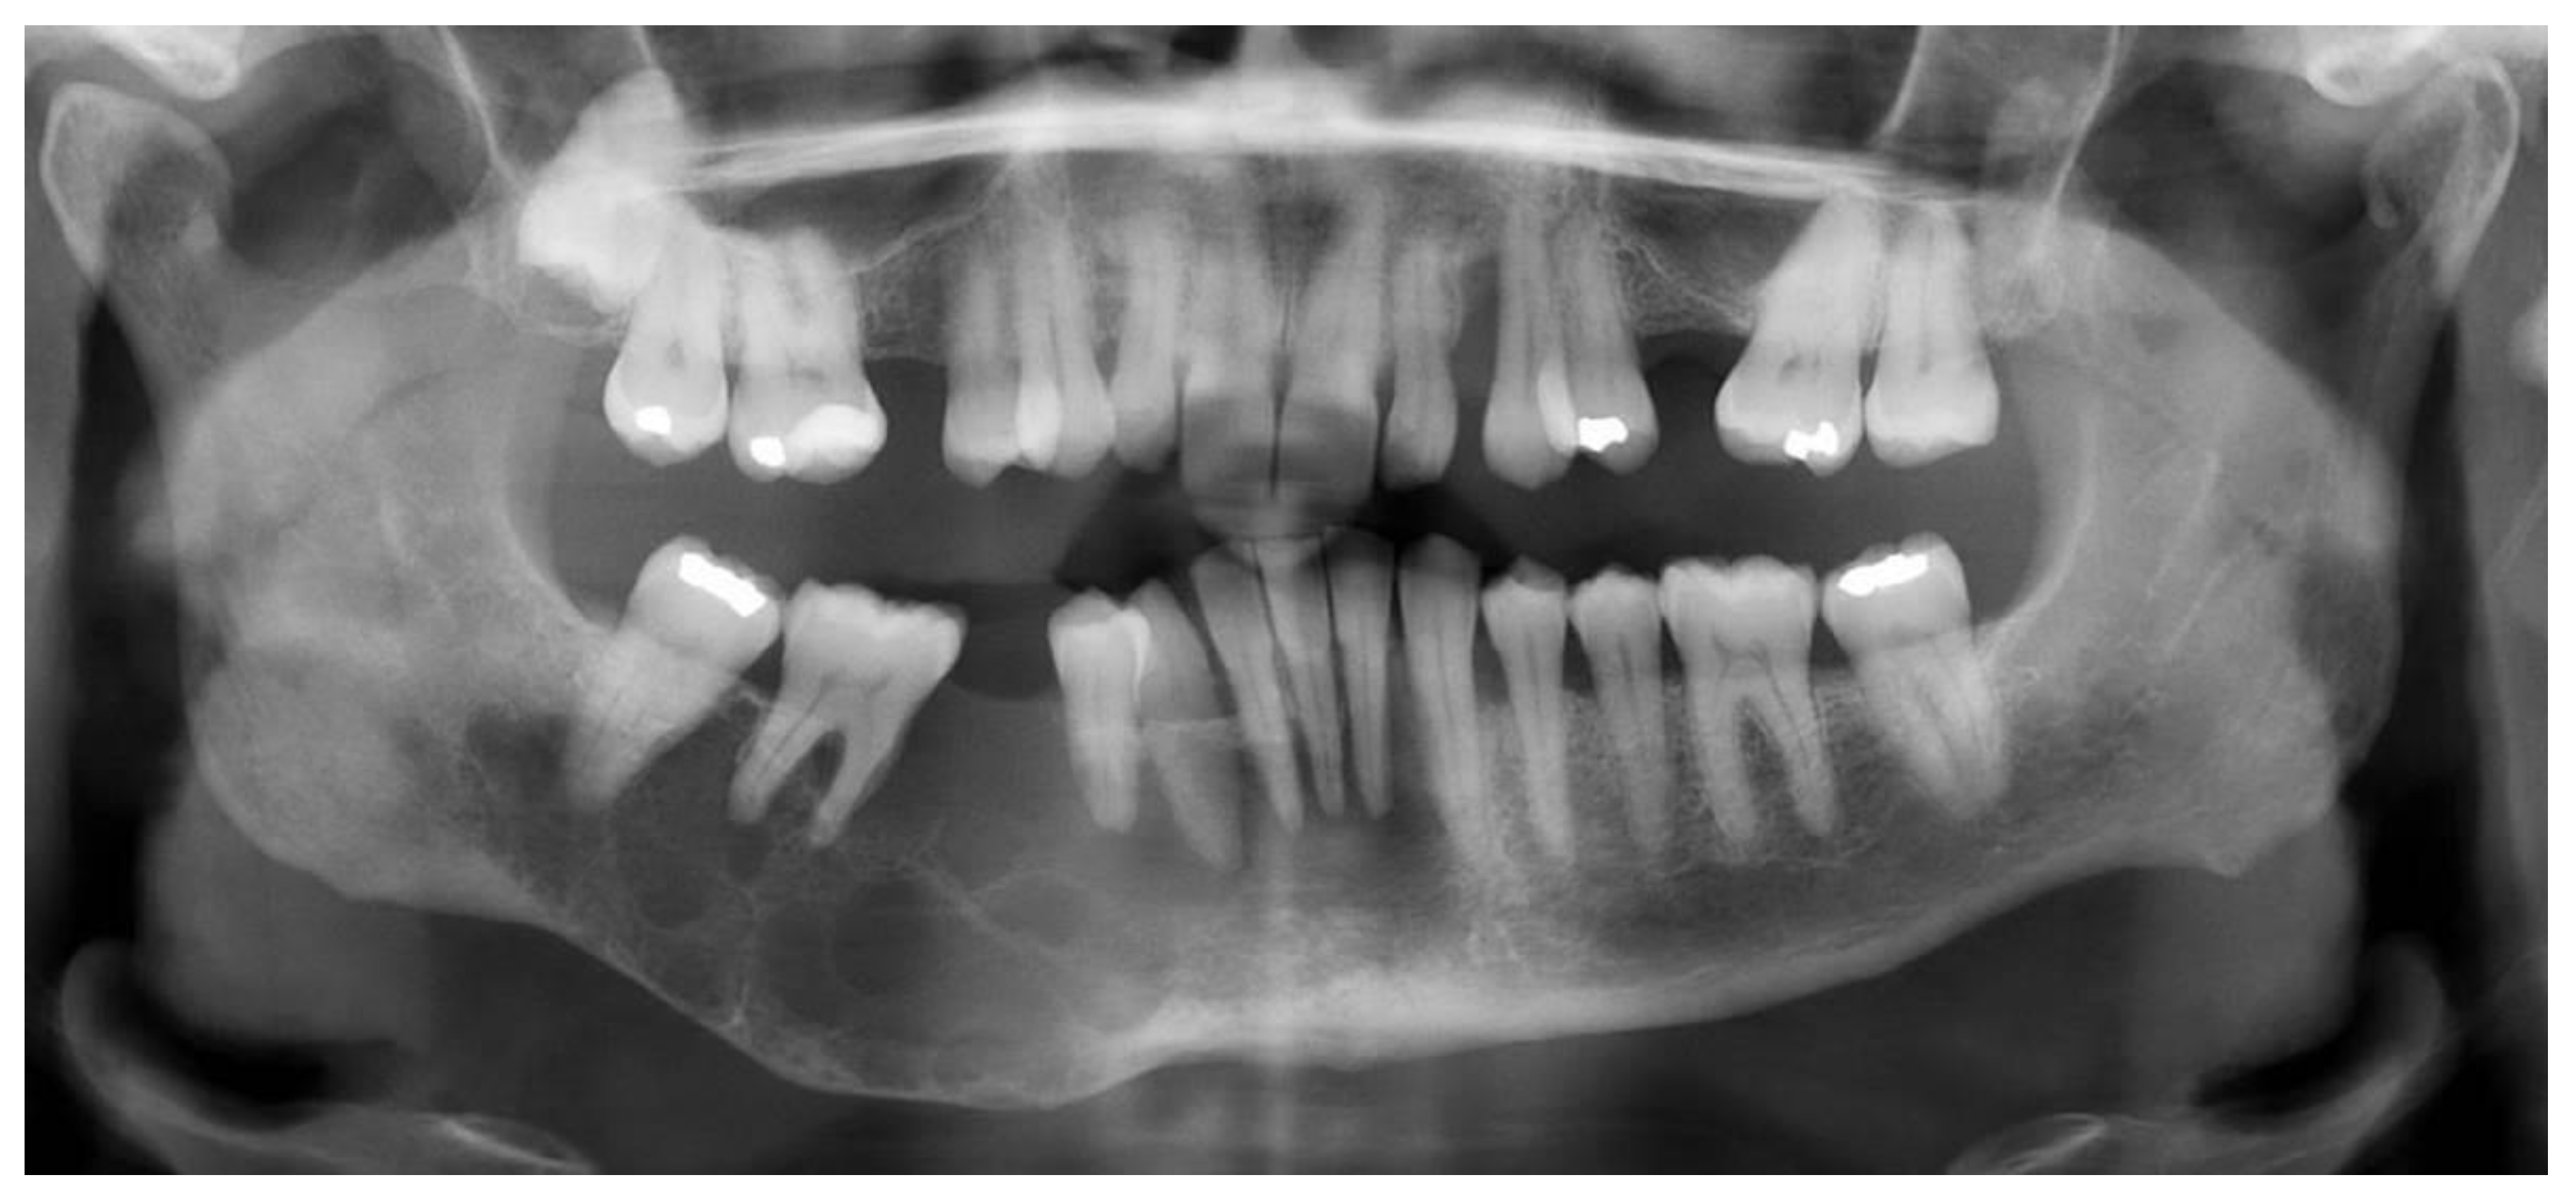

2.2. Case 2